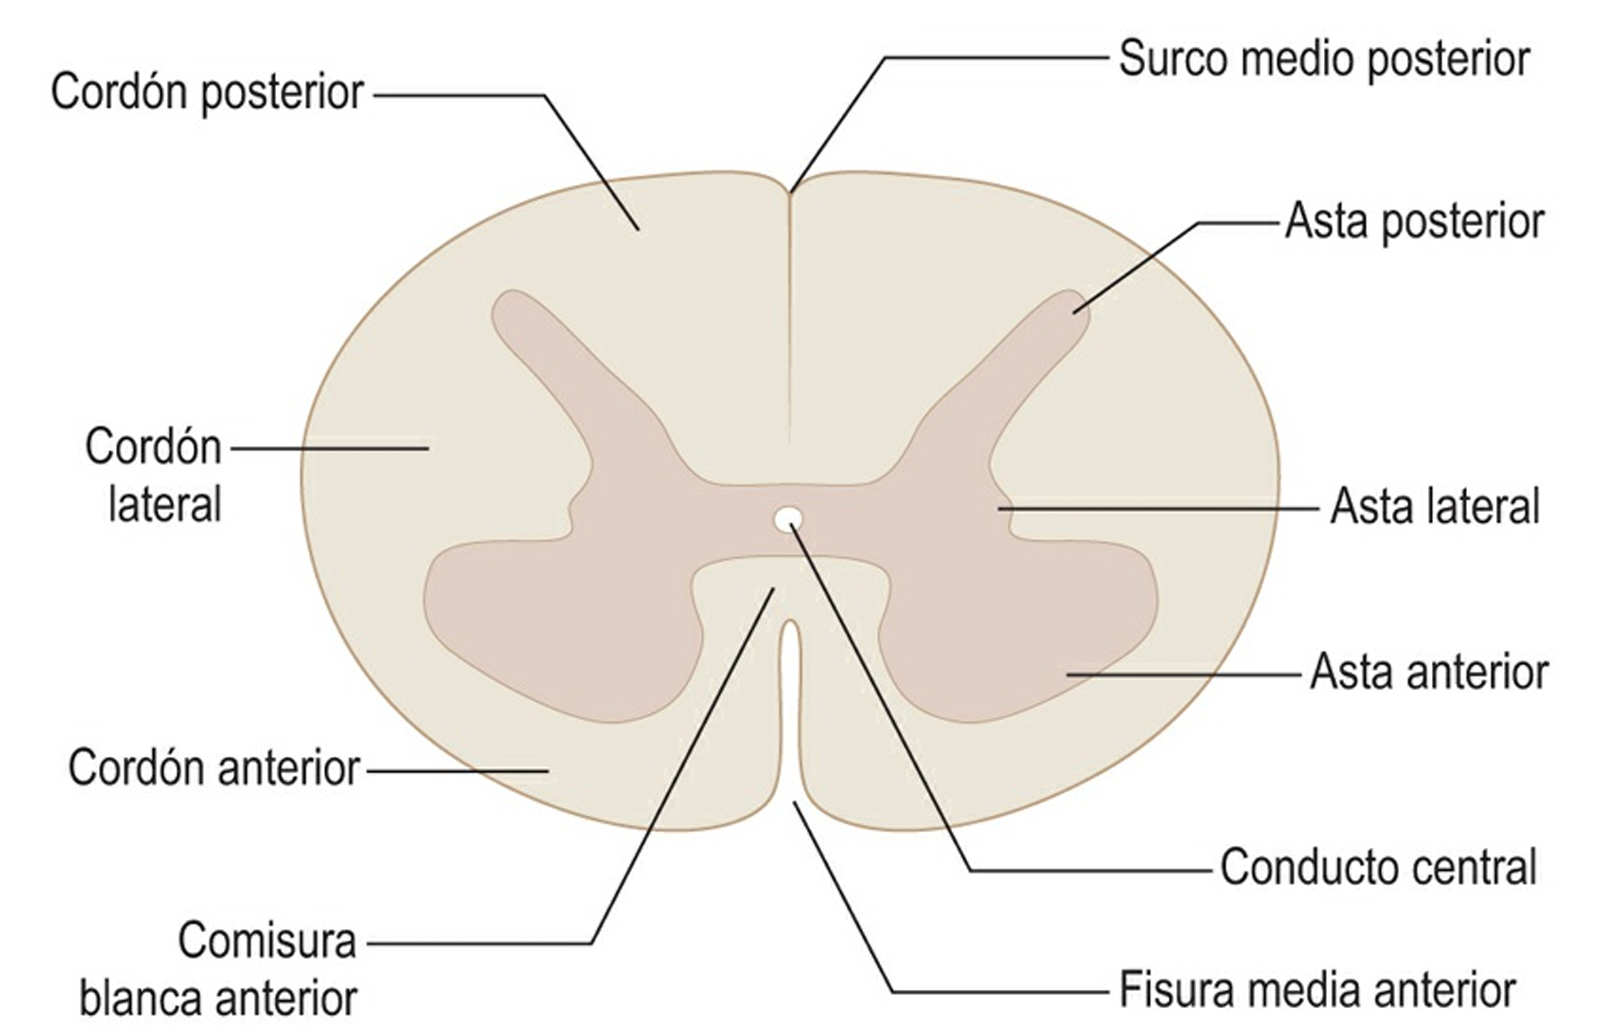

Las caras laterales de la médula espinal también desempeñan un papel vital, siendo afectadas por las salidas de las raíces nerviosas que emergen a través de agujeros en la columna vertebral, denominados agujeros de conjunción. Estas regiones laterales alojan tanto la sustancia gris como la sustancia blanca de la médula. La sustancia gris contiene cuerpos celulares de neuronas, mientras que la sustancia blanca comprende las fibras nerviosas que conectan diversas partes del sistema nervioso.

Entre la fisura mediana anterior y los surcos anterolaterales, a los lados del plano mediano, se encuentran los dos cordones anteriores, uno derecho y otro izquierdo. Estos cordones contienen fibras nerviosas que forman parte del sistema nervioso central y están involucradas en la transmisión de señales motoras. Los cordones anteriores contribuyen significativamente a la función motora de la médula espinal, desempeñando un papel esencial en la coordinación de los movimientos corporales.

En el plano mediano de la cara posterior de la médula espinal, se visualiza un surco poco profundo conocido como el surco mediano posterior, que se extiende a lo largo de toda la longitud de esta cara. Este surco se profundiza gracias a la presencia de un tabique denominado el tabique mediano posterior. El tabique mediano posterior tiene la función de dividir la cara posterior de la médula en dos cordones posteriores: uno derecho y otro izquierdo. Esta organización estructural desempeña un papel crucial en la coherencia anatómica de la médula espinal.

Cabe destacar que cada cordón posterior de la cara posterior de la médula espinal se encuentra dividido hasta la segunda vértebra torácica por el surco intermedio posterior. Esta división resulta en la formación de dos estructuras distintas: el cordón medial o fascículo grácil y el cordón lateral o fascículo cuneiforme. Ambos cordones están implicados en la transmisión de información sensorial, siendo el fascículo grácil responsable del transporte de señales desde la mitad inferior del cuerpo, mientras que el fascículo cuneiforme se encarga de llevar señales desde la mitad superior.

Estas caras laterales corresponden a los cordones laterales de la médula espinal. Los cordones laterales son regiones anatómicas importantes que contienen fibras nerviosas y desempeñan funciones específicas en la transmisión de información dentro del sistema nervioso central.